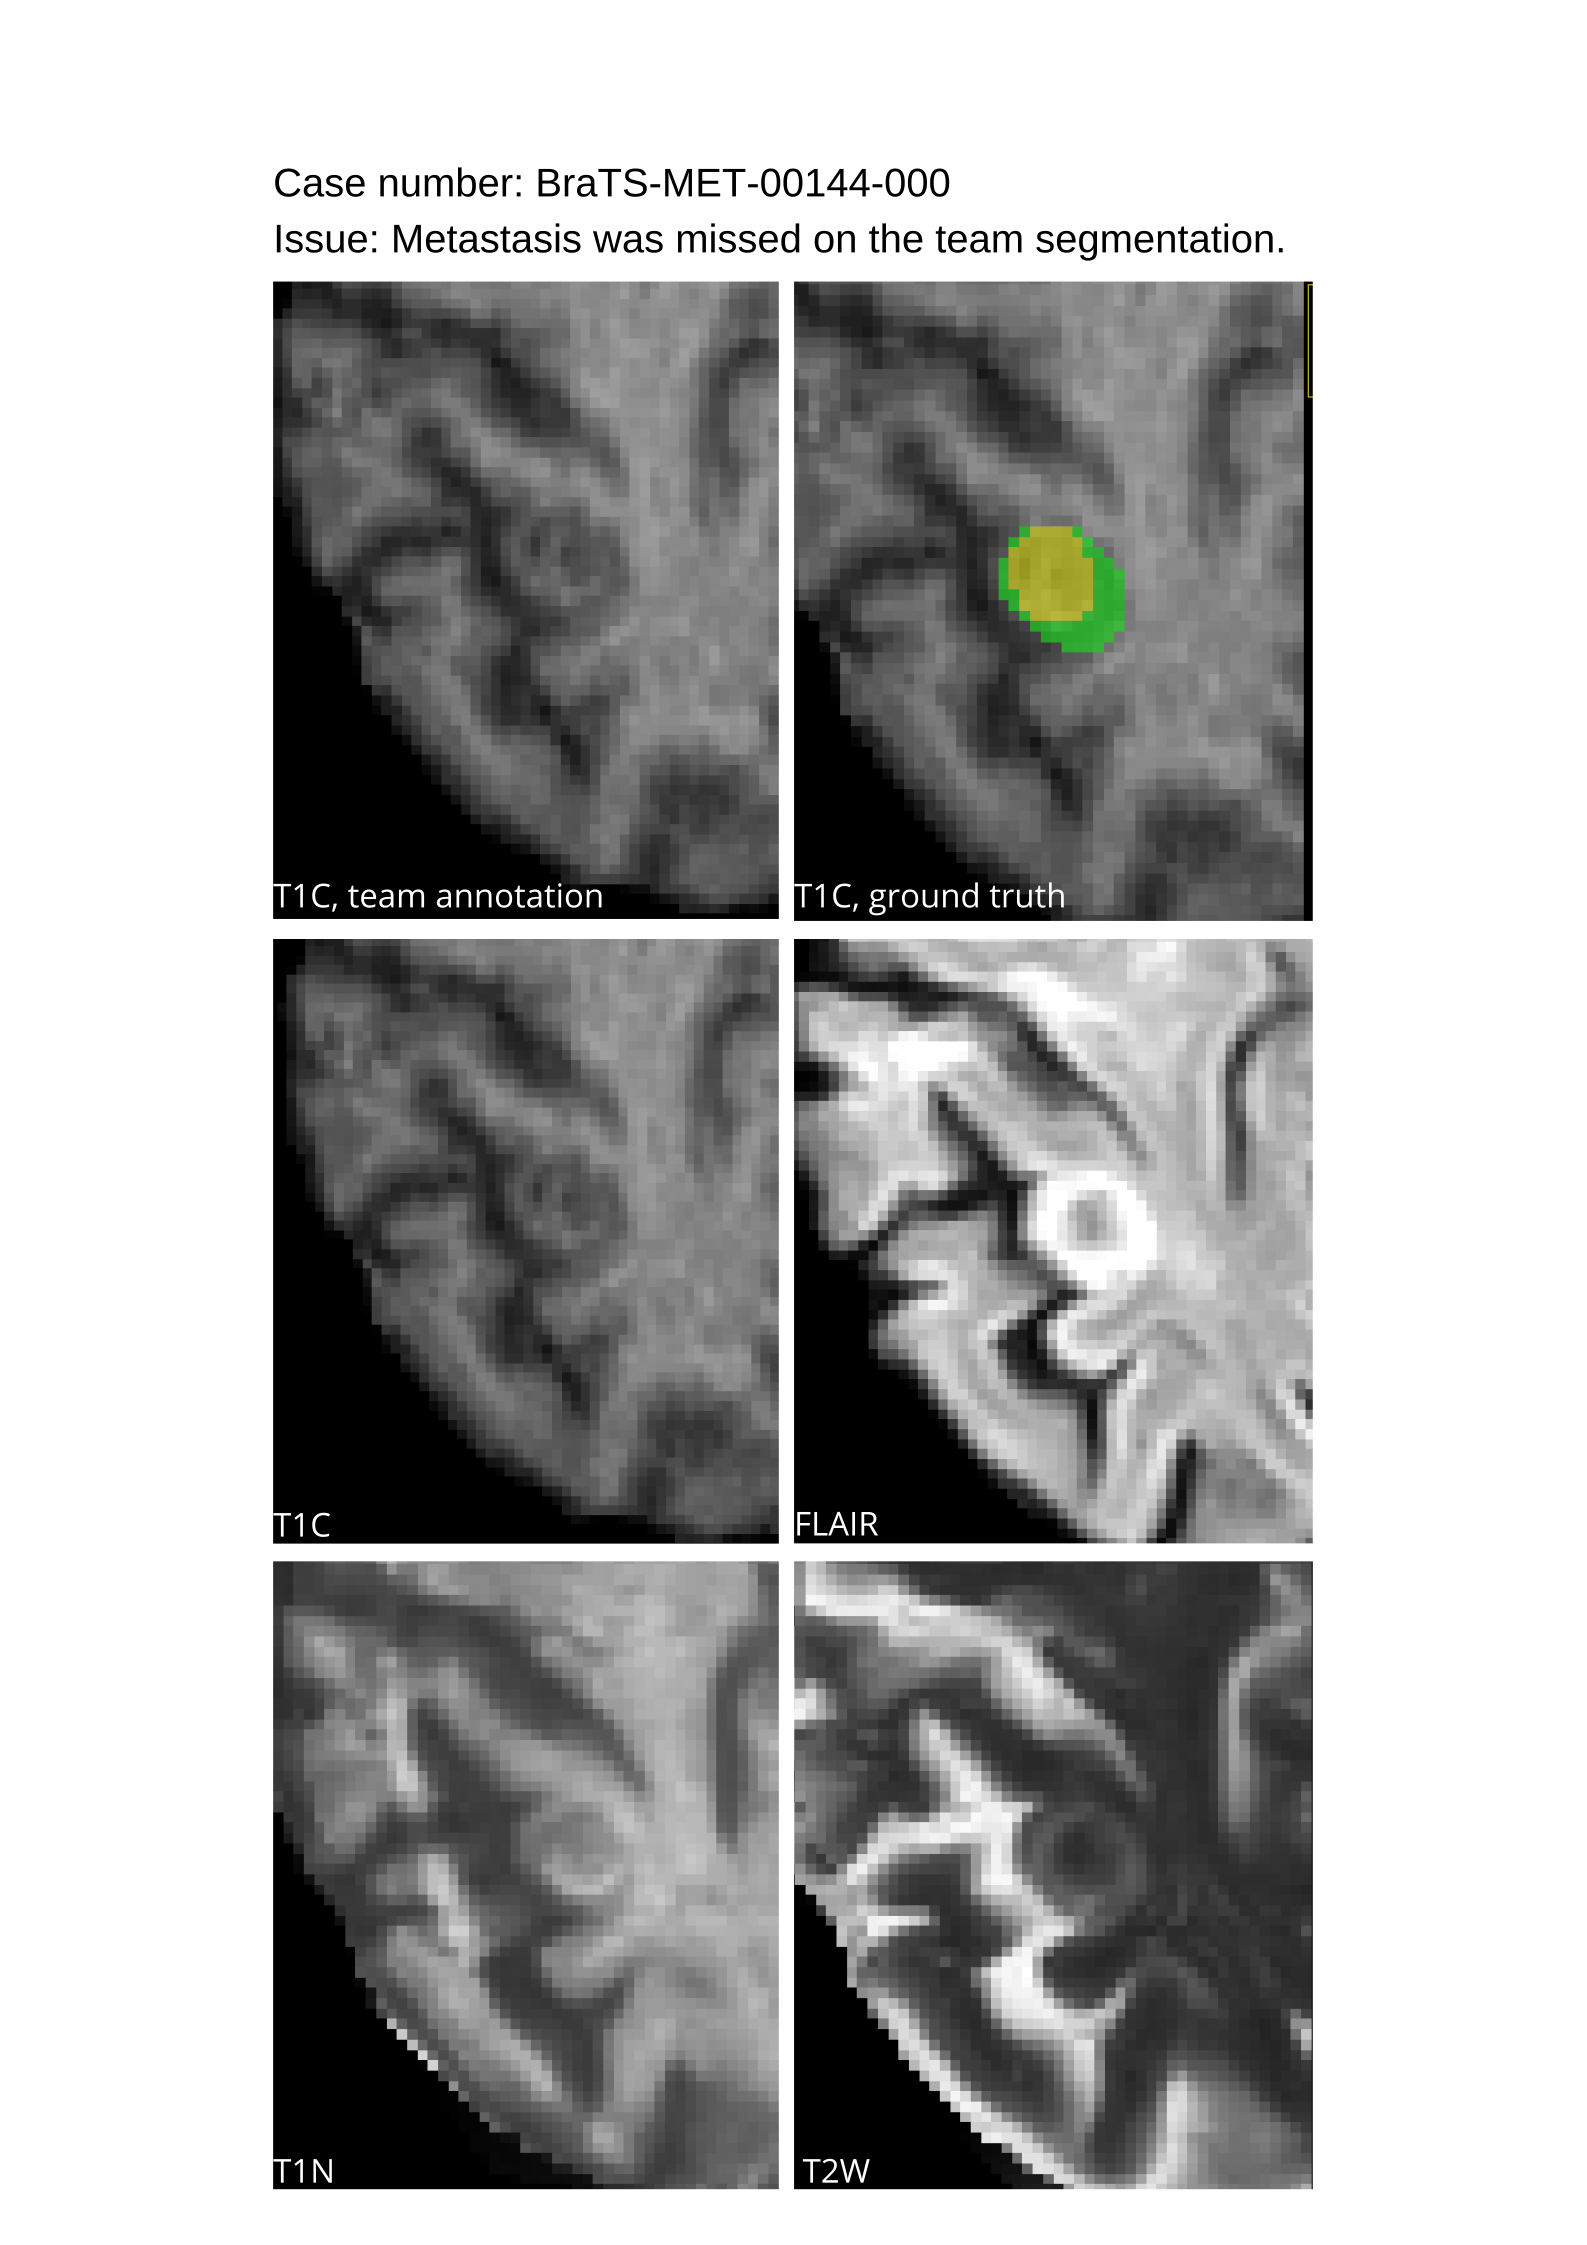

Table 4 provides the relative ranking for each team. Team NVAUTO ranked first in the challenge, with an average rank across subjects of 7.9 and a PatientWise mean of 0.38. Team SY placed second with a PatientWise mean of 0.41 across all patients. The supplementary material depicts the pitfall cases with figures illustrating the false positives or missed lesions.